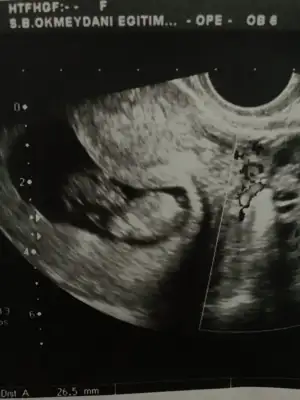

Her iki doktor farkli soyledi cinsiyetini 10ngun sonra kesin soyleriz dedi son fotograflar yeni bacak arasi net dikattli bakinca belki fikrin netlesir belki canimSanki erkek gibi 12 yada 13 hafta usgde paylaşın![]()

Usg net değil kaç hafta usg 12 13 de paylaşırsınız emin değilim sanki kızKızlar bizede tahminde buluna bilir misiniz vajinal ultrason![]()

11 12 13 hafta usg olmalı burada 14 haftada nub oluşmuş oluyor sanki emin değilim erkek gibi gibi istediğim usg leride paylaşın14 haftalık tahmin edermisiniz

Karından bakıldı ise kız siz yinede 11 12 13 hafta nub için usg paylaşın

Ancak 2 hafta sonra gidebilirim sokaga cikma yasagi olmazsaEvet burada daha önceki usg de nubu erkek gibi bacak arası usg göremedim buradaama 12 13 hafta usg istedim çünki net değildi halada 12 13 hafta usg bekliyorum

Net değil 12 13 haftada paylaşın sanki eminde değilim erkek gibi gibi